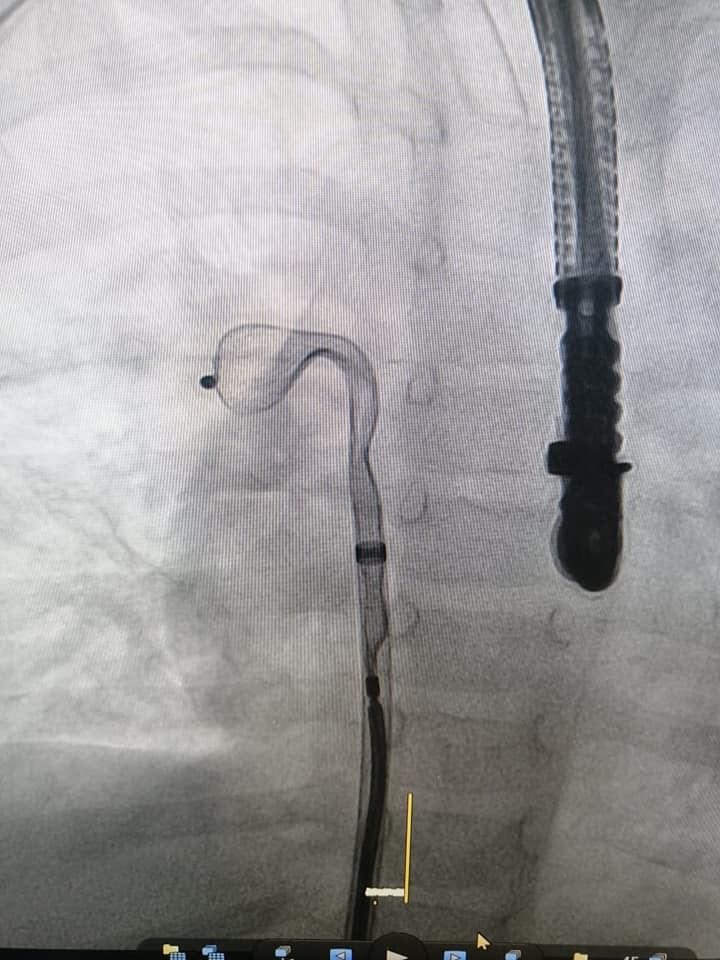

حيث أجرى د. داني يوسف المتخصص في امراض القلب عند الاطفال وفريقه الفني عمليه لطفلة تبلغ من العمر سنتين ونصف وتزن ١٠ كلغ وهي تعاني من تشوه قلبي منذ الولادة

(ASD CLOSURE)

وتحتاج الى عملية جراحية لاغلاق الفتحة بين الأذين الأيمن والأذين الأيسر وقد اجري هذا العمل الطبي التداخلي interventional therapy دون إستخدام الجراحة عبر تقنية البالون المساعد من أجل وضع الجهاز في مكانه الصحيح بدل من اجراء عملية جراحية لتعتبر هذه العملية من العمليات النادرة لهذه المرحلة العمرية حيث تنفرد مستشفى الرسول الاعظم بأطباء متخصصين ينفذون هذا النوع من العمليات ولجميع الاعمار